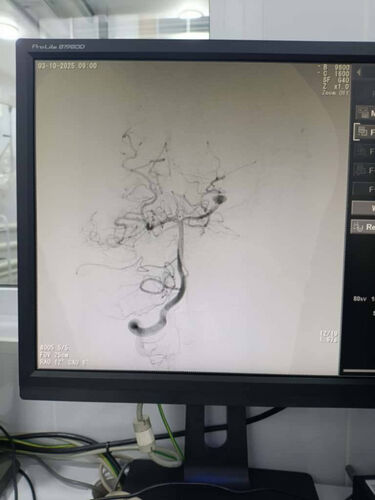

Angiographic diagnostics were performed during the preoperative stage, which allowed the size and location of vascular anomalies to be determined and the optimal endovascular tactics to be selected for each patient.

In the treatment of aneurysms, endovascular occlusion was performed while maintaining the patency of the main vessels, and in arteriovenous malformations, point embolization of the pathological node was performed to prevent the risk of hemorrhage. All manipulations were performed under the control of digital subtraction angiography.

After the operations, a follow-up angiographic assessment was performed, confirming the successful exclusion of pathological foci from the bloodstream and the absence of complications. All children recovered safely from anesthesia and were transferred to the intensive care unit for observation. According to the doctors, the patients’ condition is stable, no complications have been noted, and recovery is progressing actively.